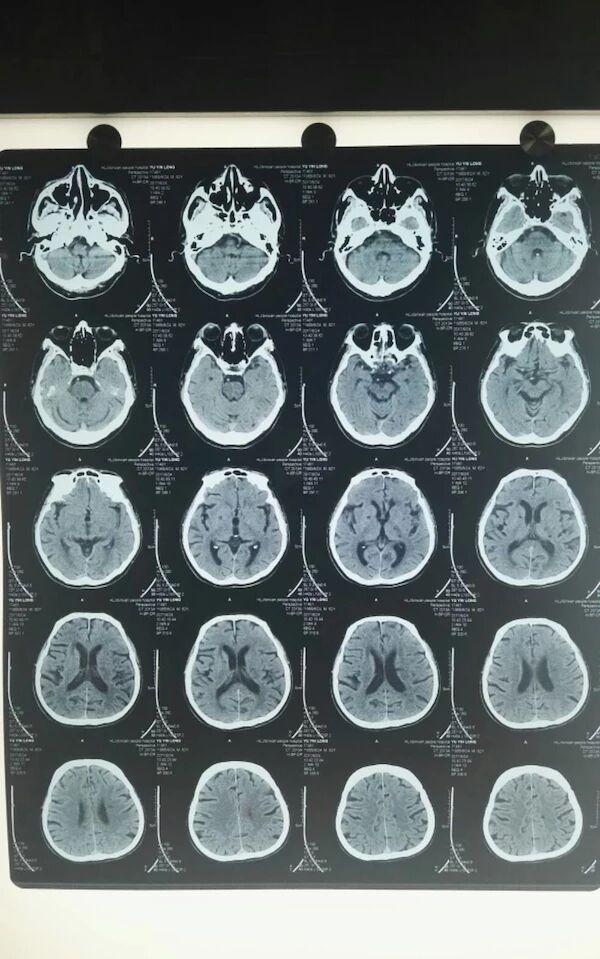

于某,男患,60岁,既往吸烟饮酒史,否认高血压、糖尿病病史,否认心脑血管病病史,入院心电图显示无房颤,2017年6月24日10点左右劳动中起病,突发言语不清,右半身无力,发病5小时,Nihss评分15分,行多模核磁小时左侧大脑中动脉急性闭塞,DWI和ADC显示仍然有可挽救的半暗带,发病6小时全麻下股动脉穿刺,取栓一次成功!

手术前的CT和多模MR